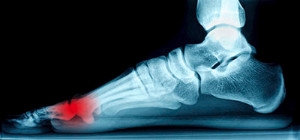

Who is at Risk for Heel Spurs?

A heel spur is caused by a calcium deposit that forms on the bottom of the heel. While many people experience no symptoms, heel spurs can be painful. Pain levels for heel spurs often vary throughout the day. Some people are more prone to getting heel spurs than others. If you have walking abnormalities that put excess pressure on the heel area, you may be at risk for this condition. Runners and joggers are known to get heel spurs, as well. Another group of people who may experience heel spurs are those who are overweight. Many times, heel spurs arise in conjunction with plantar fasciitis. If you have plantar fasciitis, you may experience heel spurs if you have diabetes, do short bursts of exercise, or spend much of the day on your feet. If you think you may have a heel spur, it is suggested that you contact a podiatrist.

Heel spurs are formed by calcium deposits on the back of the foot where the heel is. This can also be caused by small fragments of bone breaking off one section of the foot, attaching onto the back of the foot. Heel spurs can also be bone growth on the back of the foot and may grow in the direction of the arch of the foot.

Older individuals usually suffer from heel spurs and pain sometimes intensifies with age. One of the main condition's spurs are related to is plantar fasciitis.

Pain

The pain associated with spurs is often because of weight placed on the feet. When someone is walking, their entire weight is concentrated on the feet. Bone spurs then have the tendency to affect other bones and tissues around the foot. As the pain continues, the feet will become tender and sensitive over time.

Heel spurs are calcium deposits that cause bone protrusions on the heel bone. Heel spurs are usually associated with plantar fasciitis, which occurs when the plantar fasciitis in the foot becomes inflamed. Typically, heel spurs don’t cause any symptoms. However, they can produce chronic or intermittent heel pain. Those who have had the condition often describe the irritation as a stabbing pain.

There are risk factors that may make you more likely to develop heel spurs. People who have abnormal walking gaits, run and jog on hard surfaces, are obese, or wear poorly fitting shoes are more likely to develop heel spurs.

The pain associated with heel spurs often decreases the more you walk. However, a recurrence of pain after an extended period of rest or walking is likely to occur with this condition. Those with severe heel spur pain may opt to go the surgical route for treatment.  However, more than 90% of those with the condition get better without surgical treatment. If you have a heel spur and want to know if surgery is right for you, you should go to your podiatrist and he or she will be able to conduct a pre-surgical test or exam to determine if you are an optimal candidate for surgery.